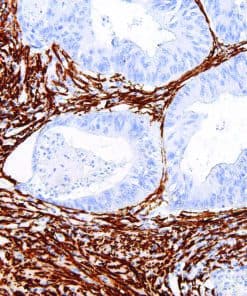

Thymidylate Synthase

Thymidylate Synthase (TS) is a crucial enzyme responsible for the synthesis of 2′-deoxythymidine-5′-monophosphate (dTMP) a precursor for thymidylate which is necessary for DNA replication and repair from 2′-deoxyuridine-5′-monophosphate (dUMP). In terms of cancer, TS is an important target for cancer treatment as the inhibition of TS and therefore nucleotide synthesis necessary for cell growth has shown to be a vital part for successful treatment against colorectal, pancreatic and breast cancers.

| Clone | IHC697 |

| Source | Mouse Monoclonal |

| Positive Control | Colon Cancer |

| Dilution Range | 1:100 – 1:400 |